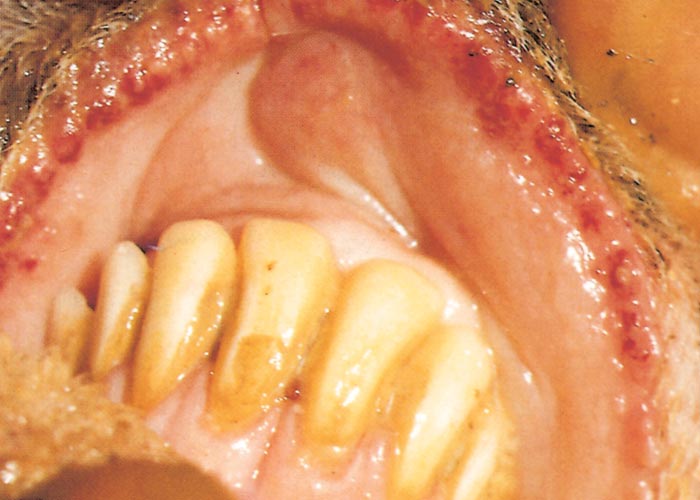

In severe cases the lesions progress and result in excoriations and erosions on the muzzle and nostrils and in the mouth (Figures 7 to 11) particularly at sites subject to friction, such as parts of the cheeks and tongue adjacent to the molar teeth and the lower lip opposite the corner incisors (Figures 12, 13a to d). Necrotizing mouth lesions result in foetid breath, which is sometimes the first clinical sign observed. They also induce pain, which may cause the animal to submerge its mouth and lips in drinking water for prolonged periods. Anorexia is common and may be exacerbated in some cases by severe swelling of the tongue, which may become cyanotic (‘blue tongue’) (Figure 14) and even protrude from the mouth. Progressive weakness and emaciation follows, accompanied by rumen stasis and occasionally haemorrhagic diarrhoea before death.

Figure 10 Severe ulcerative stomatitis and gingivitis in a sheep. (Courtesy of Drs Massimo Scacchia and Giovanni Savini, Istituto Zooprofilattico Sperimentale dell’Abruzzo e del Molise "G.Caporale" Via Campo Boario, 64100 Teramo, Italia)

Figure 11 Severe necrotizing gingivitis and stomatitis. (Courtesy of Drs Massimo Scacchia and Giovanni Savini, Istituto Zooprofilattico Sperimentale dell’Abruzzo e del Molise "G.Caporale" Via Campo Boario, 64100 Teramo, Italia)

Oral lesions initially consist of hyperaemia, oedema, cyanosis and haemorrhage of the mucous membrane (Figure 14). Destruction of epithelial cells gives rise to excoriations and erosions on the inside of the lips, dental pad, cheeks and tongue (Figures 10 to 14). Many of these lesions are transient and usually disappear within days. Secondary bacterial infection is often responsible for the diphtheric necrosis of the erosions.28, 221 Microscopically, there is mononuclear cell infiltration and degeneration and necrosis of epithelial cells in which large acidophilic intracytoplasmic masses accumulate.